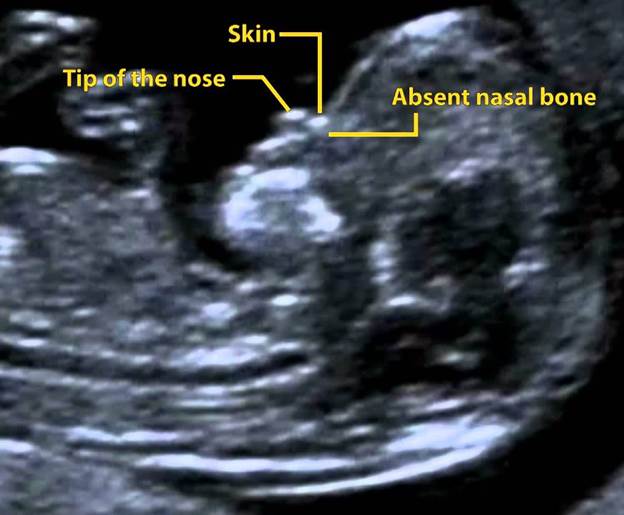

Nasal Bone Scan During Pregnancy: Top Reasons for This Essential Test

Navigating the world of prenatal care can seem daunting. However, understanding key tests, such as the nasal bone scan in pregnancy, helps ensure the best